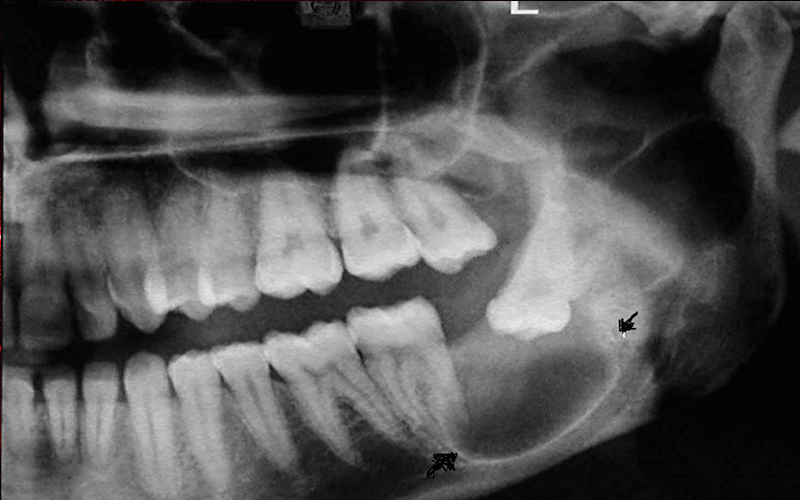

Όπως είναι γνωστό πως οι ακτινογραφίες παίζουν ένα σημαντικό ρόλο στη διάγνωση και αναγνώριση αρκετών οδοντιατρικών προβλημάτων. Στο ιατρείο της Dr. Ειρήνη Δημάδη υπάρχει το σύστημα ψηφιακής ακτινογραφίας. Με το σύστημα αυτό ένας μικρός αισθητήρας χρησιμοποιείται αντί του κλασσικού φιλμ.

Ο αισθητήρας είναι συνδεμένος σε έναν υπολογιστή, έτσι ώστε όταν η ακτινογραφία καταγράφεται η εικόνα εμφανίζεται στην οθόνη σε δευτερόλεπτα. Ένα μεγάλο πλεονέκτημα του συστήματος της ψηφιακής ακτινογραφίας είναι η μειωμένη έκθεση στην ακτινοβολία. Επειδή ο αισθητήρας είναι πολύ ευαίσθητος η έκθεση μειώνεται στο 1/10 σε σχέση με την παλαιότερη μέθοδο με το κλασσικό φιλμ. Ένα δεύτερο μεγάλο πλεονέκτημα είναι η ταχύτητα με την οποία εμφανίζεται η ακτινογραφία στην οθόνη του υπολογιστή, κερδίζοντας πολύτιμο χρόνο.

Επίσης, ο ίδιος ο ασθενής μπορεί να δει την ακτινογραφία σε υψηλή ανάλυση και να κατανοήσει καλυτέρα το πρόβλημα του. Οι ακτινογραφίες αποθηκεύονται και ο οδοντίατρος μπορεί κάθε στιγμή να τις ξαναδεί αν χρειαστεί. Η ευκολία λήψης, απεικόνισης και αποθήκευσης των ακτινογραφιών καθιστά την ψηφιακή ακτινογραφία σε ένα πραγματικά ισχυρό εργαλείο, και σε συνδυασμό με την ικανότητα του οδοντιάτρου δίνει άριστα αποτελέσματα σε πολλές θεραπείες των δοντιών και των ουλών.